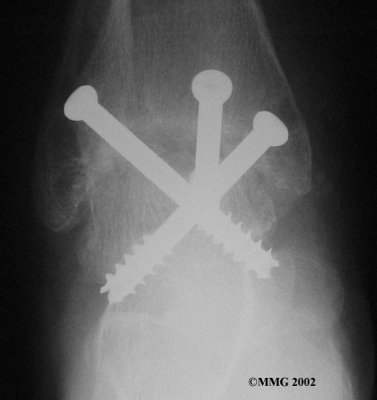

It is important when the surfaces are removed that the angles of the cut surfaces are correct. When the tibia is brought against the talus, the foot should be at a right angle to the lower leg. Once the cuts are made the bones must be held in place while they fuse. This can be done using large metal screws and metal plates if necessary. The screws are usually under the skin and are not removed unless they begin to rub and cause pain.

Inserting the screws

After ankle fusion, the physical therapists at FYZICAL East El Paso can help you learn to walk smoothly and without a limp. Although time needed for recovery varies among patients, an ankle brace will typically replace your cast after eight to 12 weeks. Your surgeon will take X-rays frequently to see if the bones are fusing together. You will probably need to use crutches during the time you wear the cast. As the fusion grows stronger, you will begin to put more weight on your foot when walking.